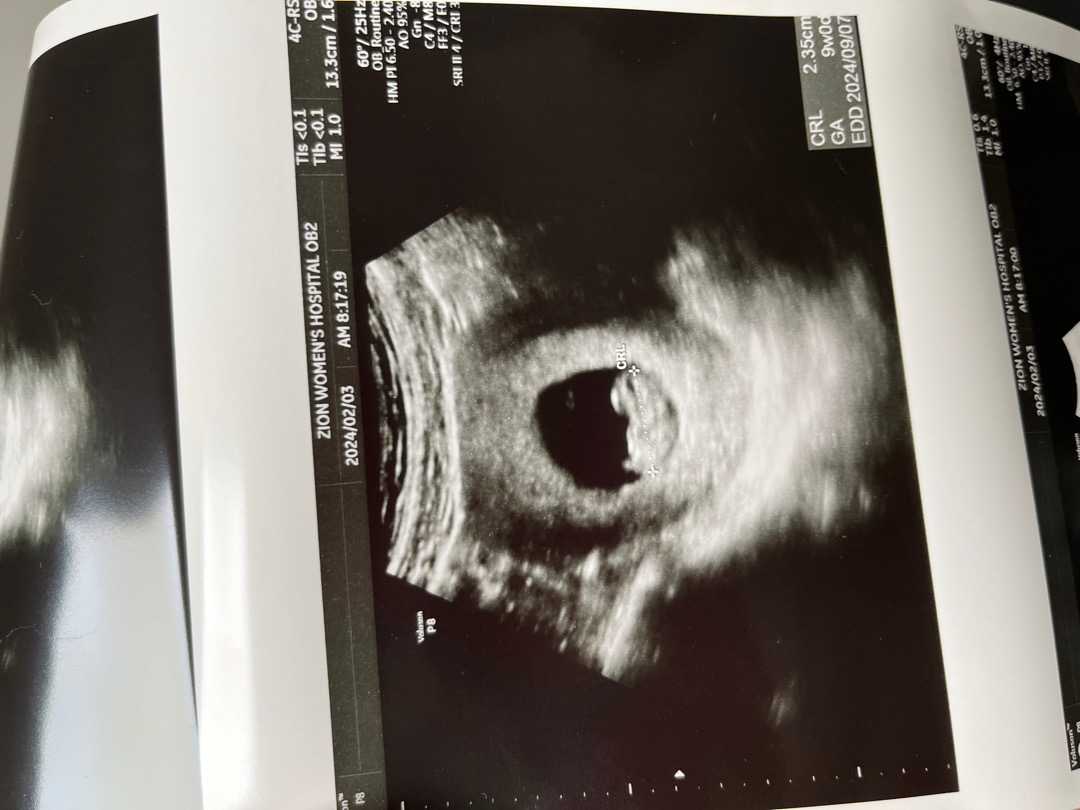

9주차 촘파🧡

1.20일에 첫심장소리듣고 2주만에 초음파보러왔는데 쪼꼬미가 그새 1cm가 자라있었답니다ㅋㅋ먼가 젤리곰이 보고싶었지만 누워있는모습이여서 아쉽긴했어요 그치만 쪼꼬만 다리보고 심쿵ㅋㅋㅋ근데 남편한테 B형독감이 옮아버려서... 오늘 타미플루랑 타이레놀 처방받고왓어요 ㅠㅠ 열나면 태아한테 안좋다그래서 걱정입니다..